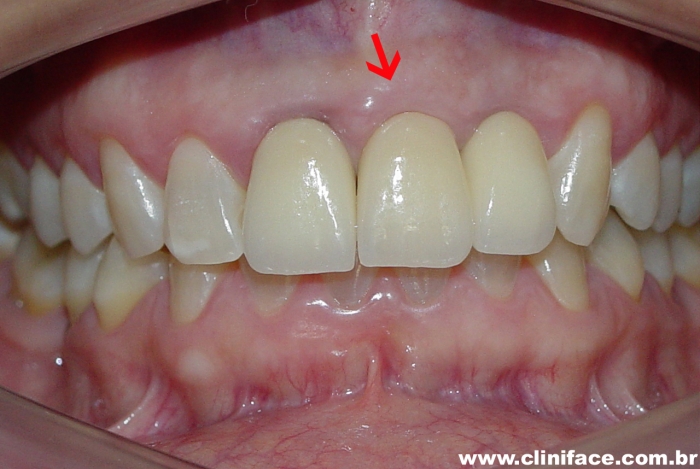

Protese fixa em porcelana no elemento 21

Sorriso final do caso terminado em agosto de 2009